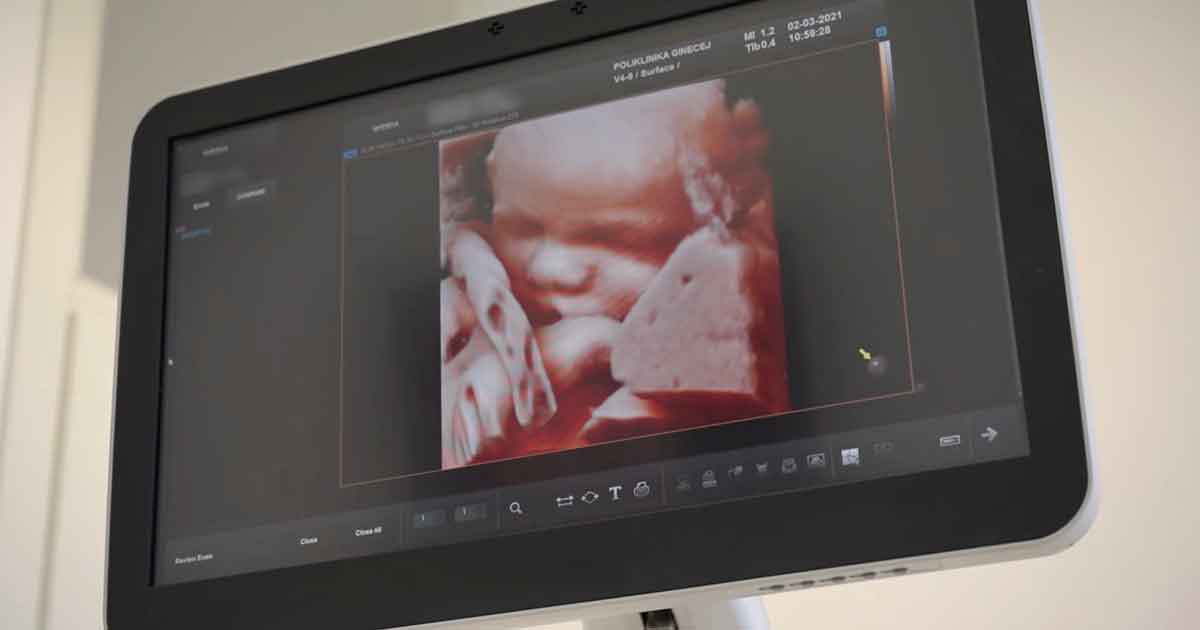

Genetički sonogram se izvodi između 11. tjedna trudnoće i 13⁺⁶ tjedna trudnoće. Ultrazvučni pregled se izvodi transvaginalnom ili rjeđe transabdominalnom sondom.

Za dijagnosticiranje velikih fetalnih abnormalnosti, doba nakon završene organogeneze, odnosno formiranja osnove svih organa, je optimalno.